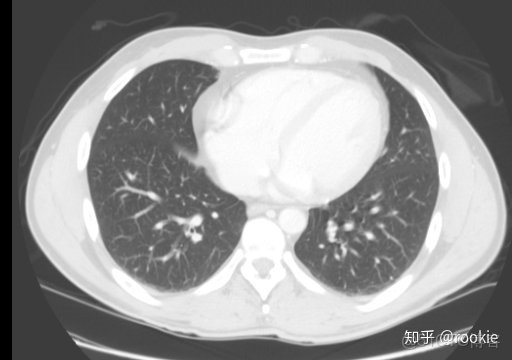

肺窗口窗口設置: (W:1600,L:-600)或(W:1500,L:-500)優點: 顧名思義,此窗口用於評估肺。靠近肺組織密度的高窗口水平(鑑於其低密度水平為低),並與寬窗口一起使用以提供良好的分辨率並可視化胸部的各種密度,例如肺實質以及相鄰的血管。

CLAHE算法增強局部對比度的X光圖像增強效果對比_#python 計算對比度_10

肺窗有助於評價肺,某些胸部病理學(如特定類型的結節)只能在這個窗口上看到。